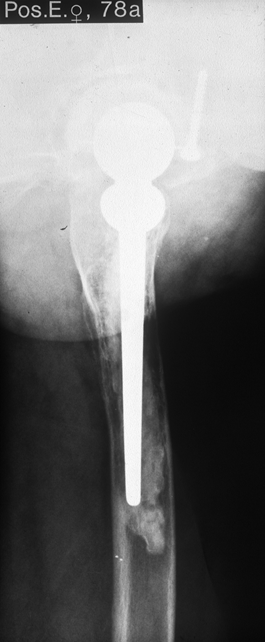

Fallbeispiel

Weiblich, 78 Jahre. Die

Bilder zeigen eine deutlich gelockerte zementierte

Hüftprothese. Der Knochen um den Zement ist stellenweiße

papierdünn

Zustand nach Austausch der

zementierten Prothese durch eine Bicon-Pfanne sowie

einen SLR-Schaft.

Die Röntgenbilder zeigen das Ergebniss nach 13 Jahren.

Die nun 91 jährige Patientin ist gut gehfähig und völlig